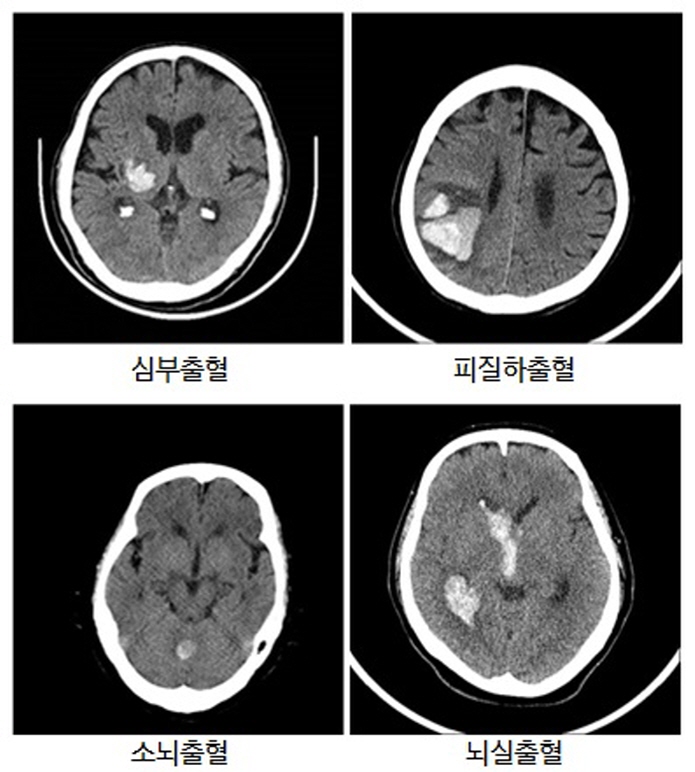

□ 심부출혈(뇌기저핵, 시상)

- 증상 : 고혈압성 뇌출혈이 호발되는 부위로 뇌내출혈의 50% 이상을 차지하며 편측 마비, 편즉 감각이상, 언어장애(우성반구시)가 발생할 수 있습니다.

□ 대뇌 피질하출혈

- 증상 : 주로 고령에서 발생하고 고혈압보다는 아밀로이드 혈관병증이 원인입니다.

□ 소뇌출혈

- 증상 : 주로 고혈압이 원인인 경우가 많습니다. 심한 두통과 어지러움이 발생하며 마비증상 없이 균형감각 저하로 인한 보행장애를보일 수 있습니다. 출혈 후 급성 수두증이 발생하거나 뇌간 압박 시 짧은 시간 내에 혼수상태에 빠질 수 있습니다.

□ 뇌실출혈

- 증상 : 주로 뇌내출혈과 동반되어 발생합니다. 뇌실출혈만 보이는 경우 고혈압성 뇌출혈 보다는 다른 원인에 의해 출혈됐을 가능성이 높습니다. 마비 증상보다 두통, 구역, 경부강직이 나타나면 심하면 의식저하가 동반됩니다.